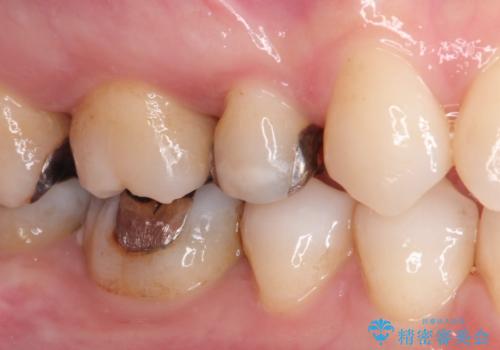

笑ったら銀歯が見える。 セラミックインレーによる治療

- 笑ったときに銀の詰め物が見えることを主訴に来院されました。

セラミックインレーにて修復を行いました。